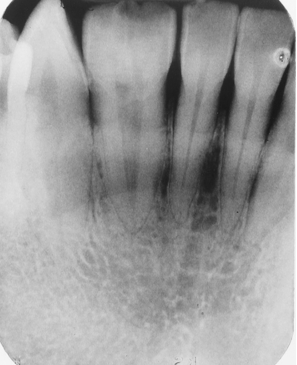

In this image you can see the two central incisors and a single lateral incisor. Clinically, there was a notch in the midincisal area. The anomaly here is

gemination

fusion

twinning

microdontia